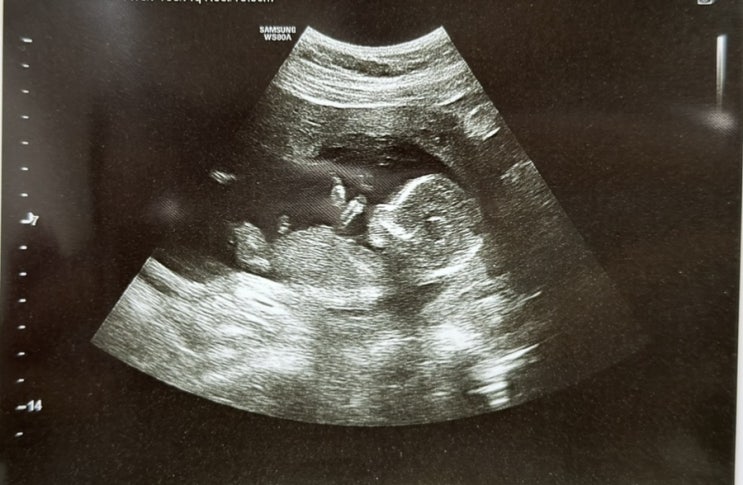

20주 정밀초음파 시기 비용 초코우유 필수일까

20주 정밀초음파 정밀초음파 시기 정밀초음파 초코우유 꿀팁 어느덧 임신 20주 차! ???❤️ 배에...